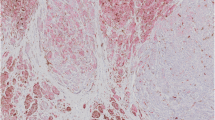

For fluorescence in situ hybridization (FISH) analysis, probes specific for CyclinD1 and cKIT genes or control centromeres were labelled with Spectrum Orange or Green (Vysis, Des Plaines, IL), respectively. Three distinct experiments were performed for each case. To be sure that FISH results were exclusively from tumor cells, histologic examination using conventional hematoxylin-eosin staining was systematically carried out on adjacent sections from paraffin-embedded tissues. Digital images were captured using an Olympus BX-61 epifluorescence microscope equipped with the appropriate filters for excitation of DAPI, Cy3 (orange) or FluorX (green), and with a COHU video and Cytovision software. Hybridization signals on at least 200 intact, well-preserved, and non-overlapping nuclei were evaluated by at least two investigators. The CyclinD1 or cKIT gene amplification was defined by the presence of at least a tetrasomic signal (≥2.0 gene copies per control centromere) in more than one tenth (>10%) of cells.

Paraffin-embedded nuclei from available tissue sections of primary melanomas were investigated by a two-colour FISH analysis, using genomic subclones corresponding to either CyclinD1 or cKIT gene loci as well as to the relative chromosome centromeres as controls. Gene amplification, as inferred by the presence of a tetrasomic signal in more than one tenth of cells (see Methods), were observed in cancer cells only. No karyotypic alteration was found in cells from normal tissues surrounding the tumours (diploid signals were consistently detected).